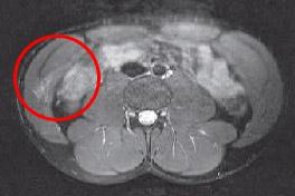

Пациент N., 32 лет; Диагноз: «Неполный разрыв прямой и косой мышц живота справа».

Лечебные сеансы начаты через 3,5 месяца после получения травмы. Диагноз подтвержден МРТ-диагностикой. Был проведен семидневный курс лечения MBST. Было достигнуто купирование болевого синдрома в ходе терапии. По данным МРТ-динамики увеличение плотности и количества мышечной ткани в области поражения.

МРТ Пациент N.,Март 2007

Пациент N.,Апрель 2007